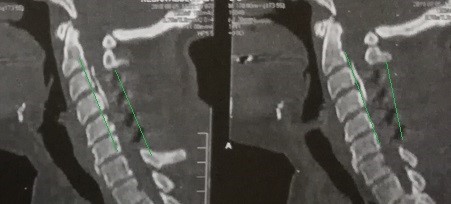

A case of a female patient in the fifth decade of life suffering from quadrilateral weakness and increased neurological reflexes due to her ossification or calcification of the dura mater against the third and fourth cervical vertebrae, and multiple cervical herniated discs as shown on CT and MRI scans.

A successful surgery was performed to expand the cervical nerve canal and stabilize the cervical vertebrae from the back, which resulted in decompression of the spinal cord in the cervical vertebrae, as shown by CT scans and MRI after surgery, and the patient recovered.